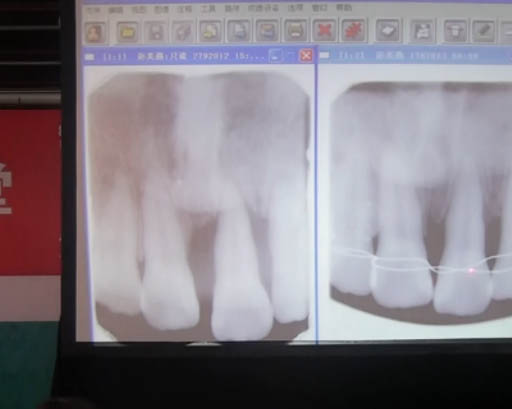

根管治療的應(yīng)用

Tilos微創(chuàng)根管治療操

根管治療前期治療中的